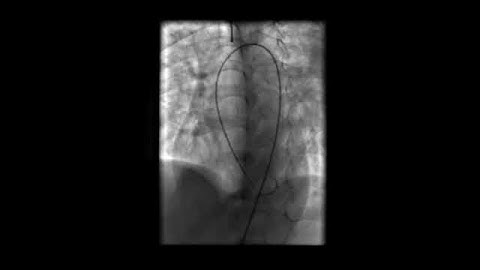

LV Angiogram Profiling Perimembranous VSD